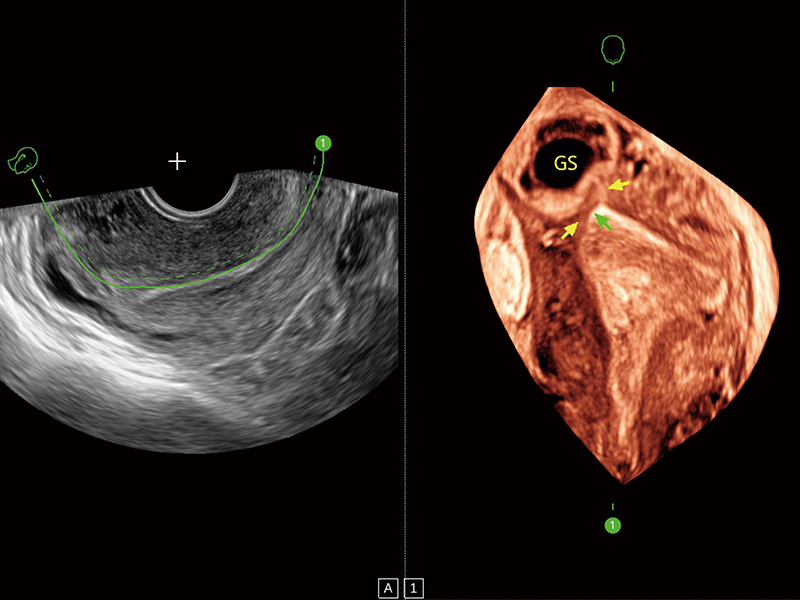

“生育问题”即关系民族复兴,也关系亿万家庭的幸福。随着婚育年龄推迟、社会压力增加等因素,越来越多人群也面临着“生不出、生不好”的问题。辅助生殖作为治疗不孕不育最有效的方法之一,也逐渐成为育儿新希望。而超声检查能为生殖需求人群的初诊评估提供宝贵的信息。 P20 Elite是玖鼎集团匠心打造的一款生殖应用型彩超。她继承玖鼎集团高端极光平台,突破性地将多款新型芯片及硬件模块进行整合,均衡了高端系统性能与小巧灵动机身。P20 Elite卓越的图像质量搭载专科探头,旨在为您提供全面的辅助生殖解决方案。

P20 Elite配备了丰富的生殖探头群和临床应用功能,在卵泡监测、穿刺取卵、胚胎移植、妊娠确认等领域,为生殖需求人群提供了新的临床机会,重新定义高端超声如何应用于生殖健康检查。